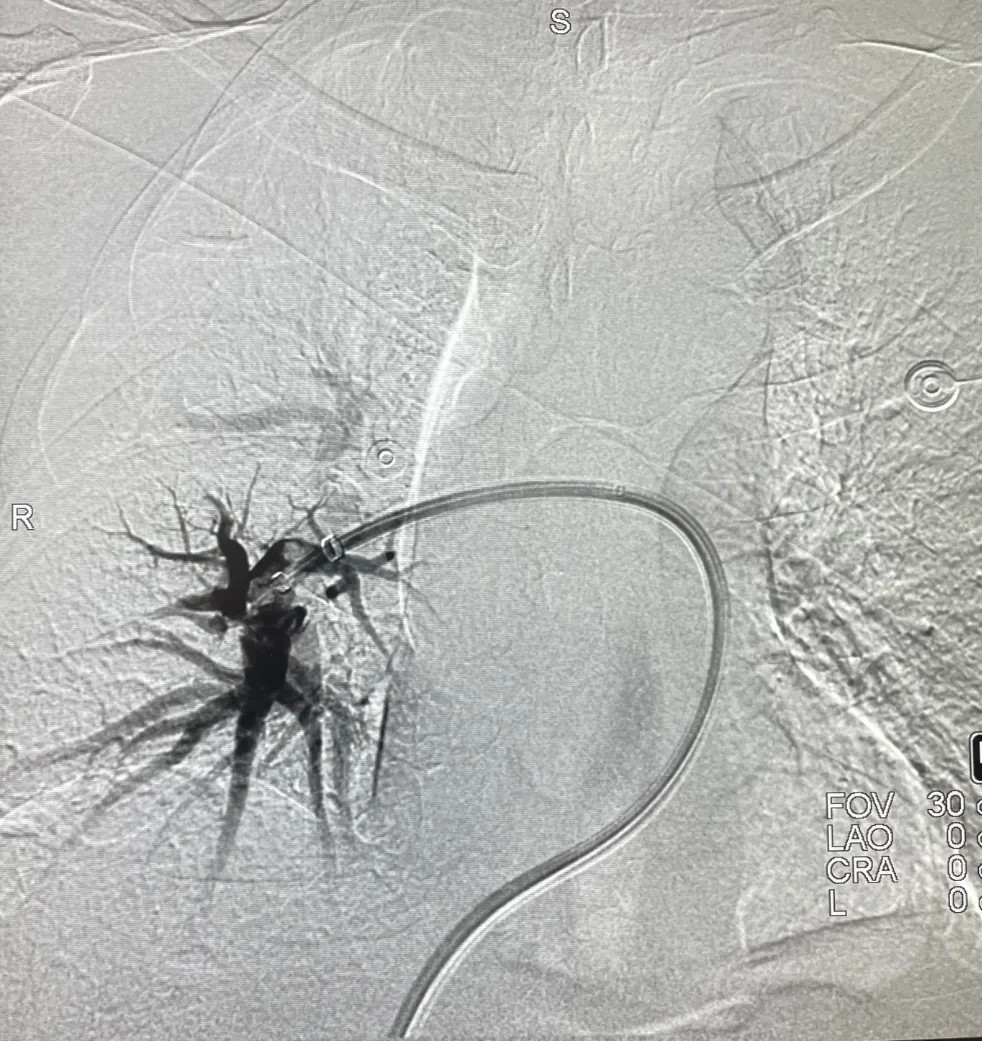

患者仰卧位,后经股静脉穿刺放置血管鞘,引入导丝和导管,建立右心房-右心室-肺动脉通路。5F导管加0.035导丝经下腔静脉、右心房、右心室,进入肺动脉,交换猪尾巴导管,分别行双侧肺动脉造影。

将Tendvia®血栓抽吸导管,沿导丝推送至肺动脉。管口贴近血栓处停止,撤出导管芯。并将Tendvia®肺动脉取栓支架沿导丝通过抽吸导管向前推送,精确导入到患者的肺动脉血栓部位。再回撤输送鞘管,支架自动膨开。连接抽吸器并形成负压,回撤取栓支架的同时旋转开关释放负压。最后,Tendvia®肺动脉取栓支架捕获和收集血栓进入抽吸导管,经负压抽吸同步的作用下,顺利为患者取出了血栓。